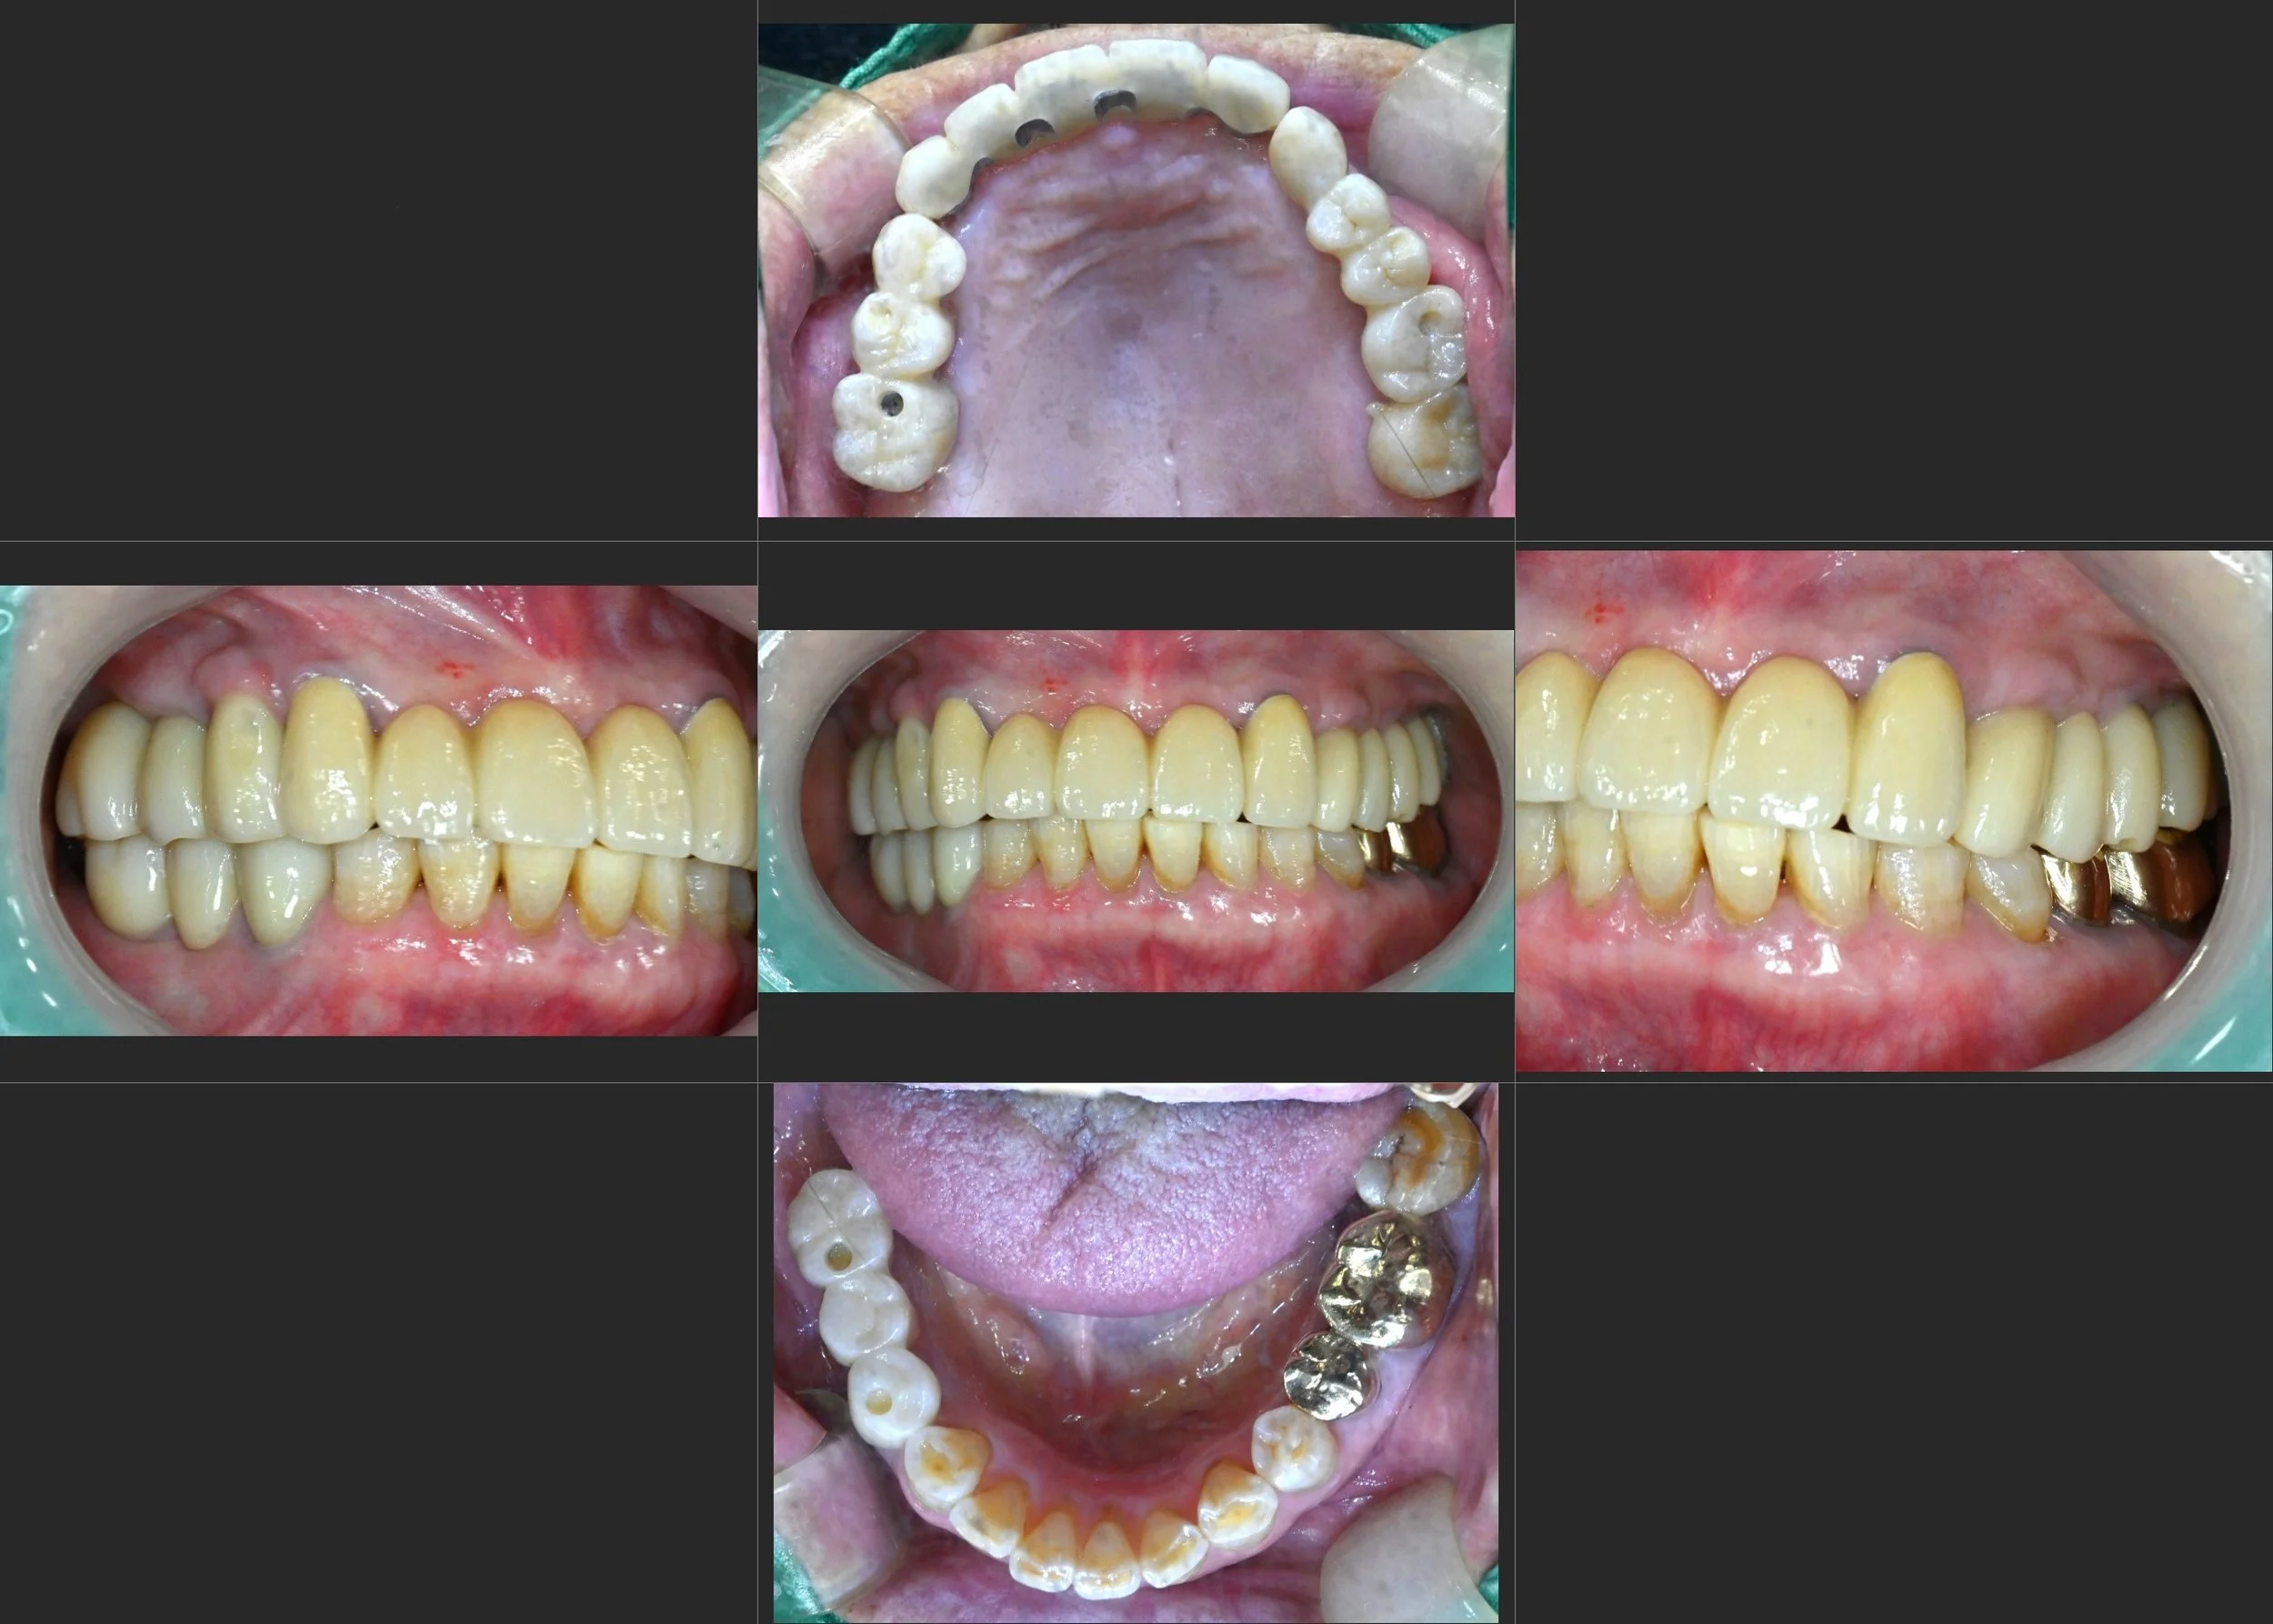

INTRA ORAL - AFTER

All failing prosthetic restorations were carefully removed.

Hopeless teeth were extracted, and implant-supported restorations were planned to re-establish occlusal stability.

Through controlled occlusal reconstruction, mandibular position was corrected and the dental midline repositioned.

The final prosthetic design focused on balanced occlusion, functional longevity,

and patient comfort without reliance on removable appliances.